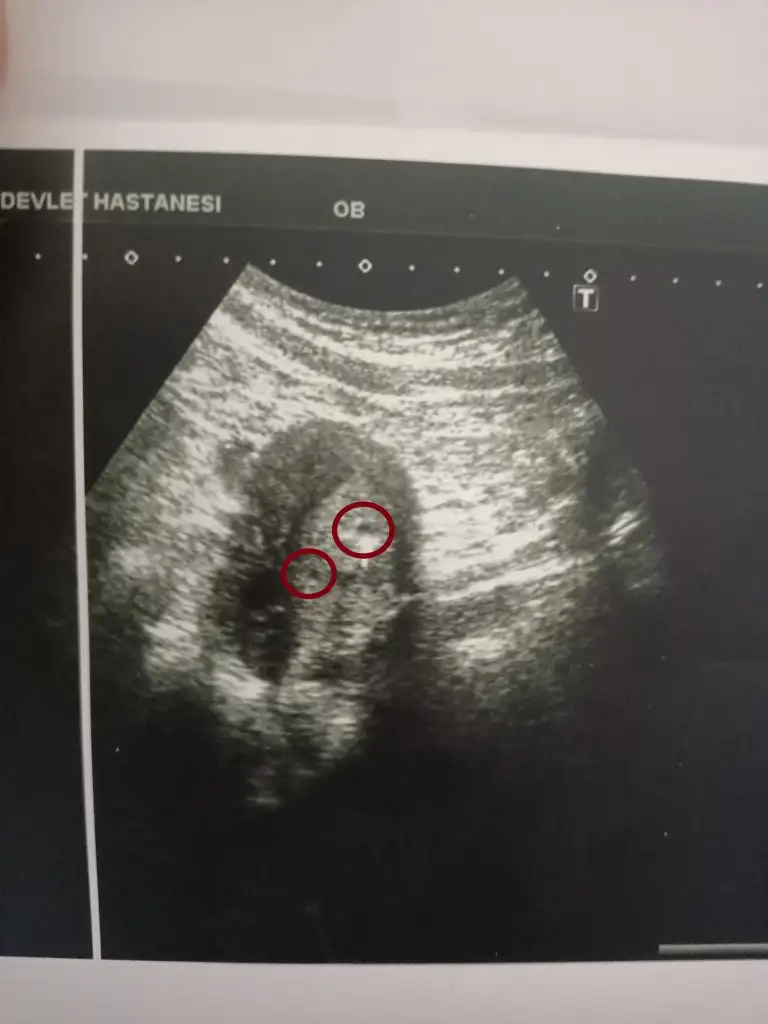

Kızlar dün doktora gittim 4+5 teyim daha çok erken ama doktor ufacık bı kese görüyorum dedi. Üstte işaretledigimden bahsetti kese bu dedi. Kan sonuçlarımda biraz yüksekti başindan beri. İlk adet günü 1200 civarıydı mesela. Sizce peki doktor üstte işaretledigim noktaya kese dediğine göre alta benim işaretledigim noktada keseye benzemiyor mu sizcede??? Siz ne düşünüyorsunuz üstteki işaretli alan kese peki alttaki işaretledigim kısımda da ikinci bir kese olabilir mi?? Sizce ikiz olabilir mi?

Korkma canm hep böyle başlıyor herşey. Konuyu açan benim ilk ogrendigimde beta HCG tam ikiye katlayacak mi diye kendimi strese soktum şimdi ise kese göründü bebek gorunecek mi diye stres yapıyorum. En son bu sabah gittigimde kese var ama daha bebek yoktu. Bukez de bir tane daha karartı var sürpriz ikinci bir kese olabilir dediler sürekli stres oluyorum işte ne olacak diye. Oyuzden Allah hepimize kolaylık versin inşallah 🙏